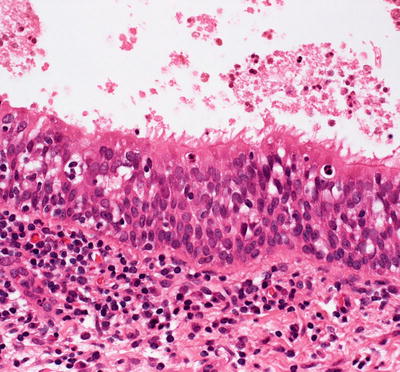

Histologic findings of median raphe cyst are those of a cystic structure within the mid-reticular dermis lined by pseudostratified columnar epithelium (Figs. 23.16 and 23.17) [47–49]. Some of the lining cells may be ciliated, columnar, or squamatized [50–52]. Mucinous cells are present in a minority of cases [48]. Rare cases are described in which abundant melanocytes are present within the cyst lining, giving the cyst a pigmented appearance [53, 54].

There are two or more layers of cells lining a cystic cavity in a median raphe cyst

Fig. 23.17

The luminal cells demonstrate a hobnail pattern of growth into the lumen in a median raphe cyst